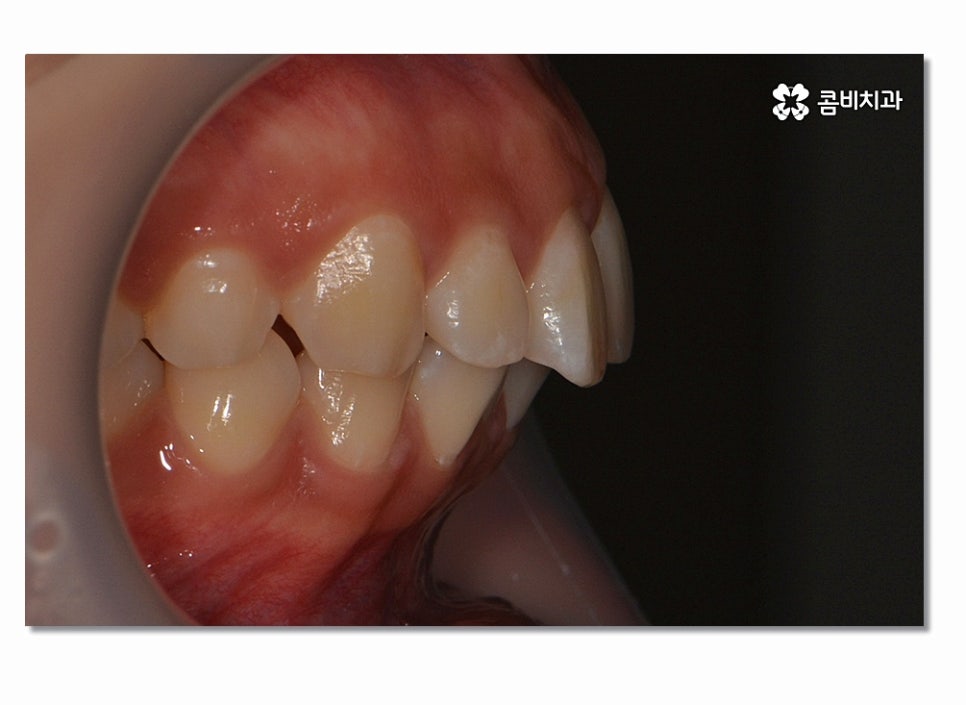

돌출입은 치아 자체가 앞으로 뻐드러진 경우와

치아, 잇몸이 모두 돌출된 경우로 구분하게 되는데 오늘은

전자의 경우로 발치를 통해 돌출입치아교정이 이뤄진

케이스에 대해서 소개 드릴 거예요.

돌출입치아교정이 시작되면 이처럼 전방으로 뻐드러진

앞니를 시간이 지남에 따라서 후방으로 이동시키면서 돌출입이

점점 개선되며 이러한 치열의 변화는 교합도 잘 맞물리도록

신경 써야 하며 얼굴 변화에 대한 부분까지 잘 생각해야 할 수 있어요.

위 사진을 보시면 치아교정 과정을 통해서 치열의 가지런함은 물론이며

측면에서 보더라도 돌출입이 많이 개선된 것을 느낄 수 있을 거예요.